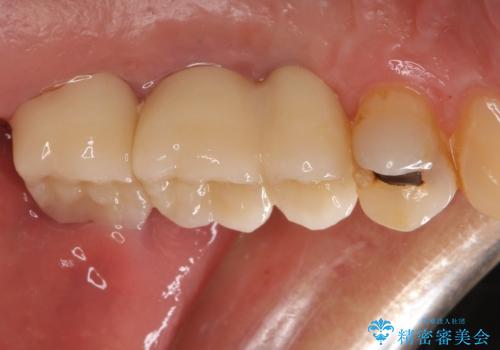

部分矯正期間中はアンカースクリューやフック、ゴムなどが粘膜にあたり、大変な思いをすることになりましたが、そのおかげでインプラント補綴した歯と最後方歯の位置が非常に良好となり、まるでご自身の歯のように咬むことができるようになりました。